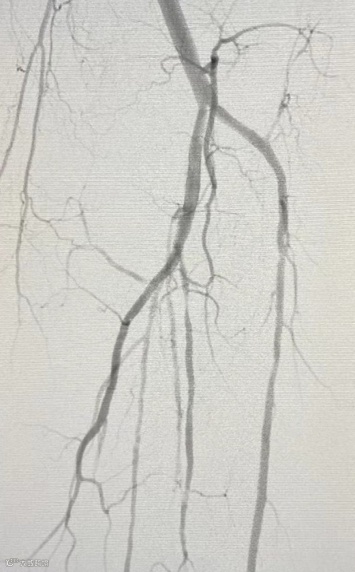

造影下抵达病变部位过程影像:导丝配合长鞘翻山至对侧,行左股动脉和膝下动脉造影,提示左股浅动脉6cm短段闭塞,考虑狭窄伴血栓形成,胫前动脉通畅,胫后动脉及腓动脉纤细,侧枝丰富。

术后造影